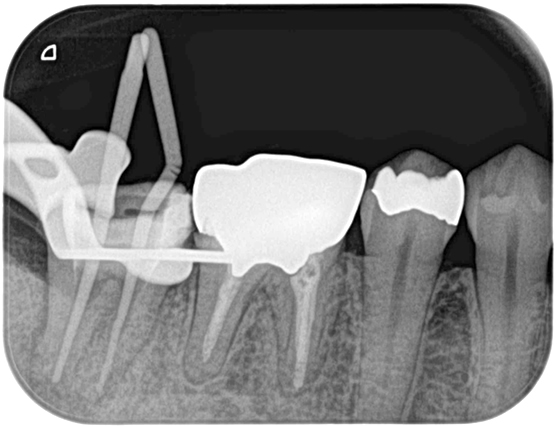

根管治療 症例8

治療前